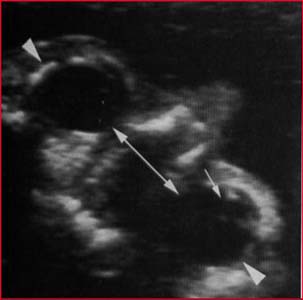

Mesure du DIO